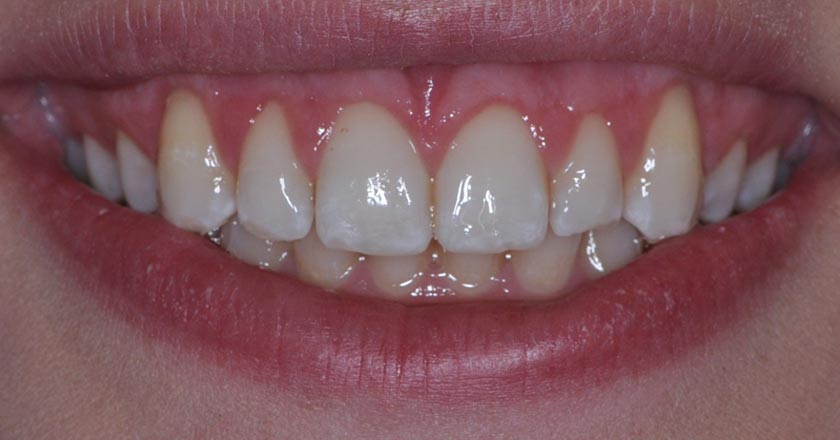

Gummy Smile - Before And After